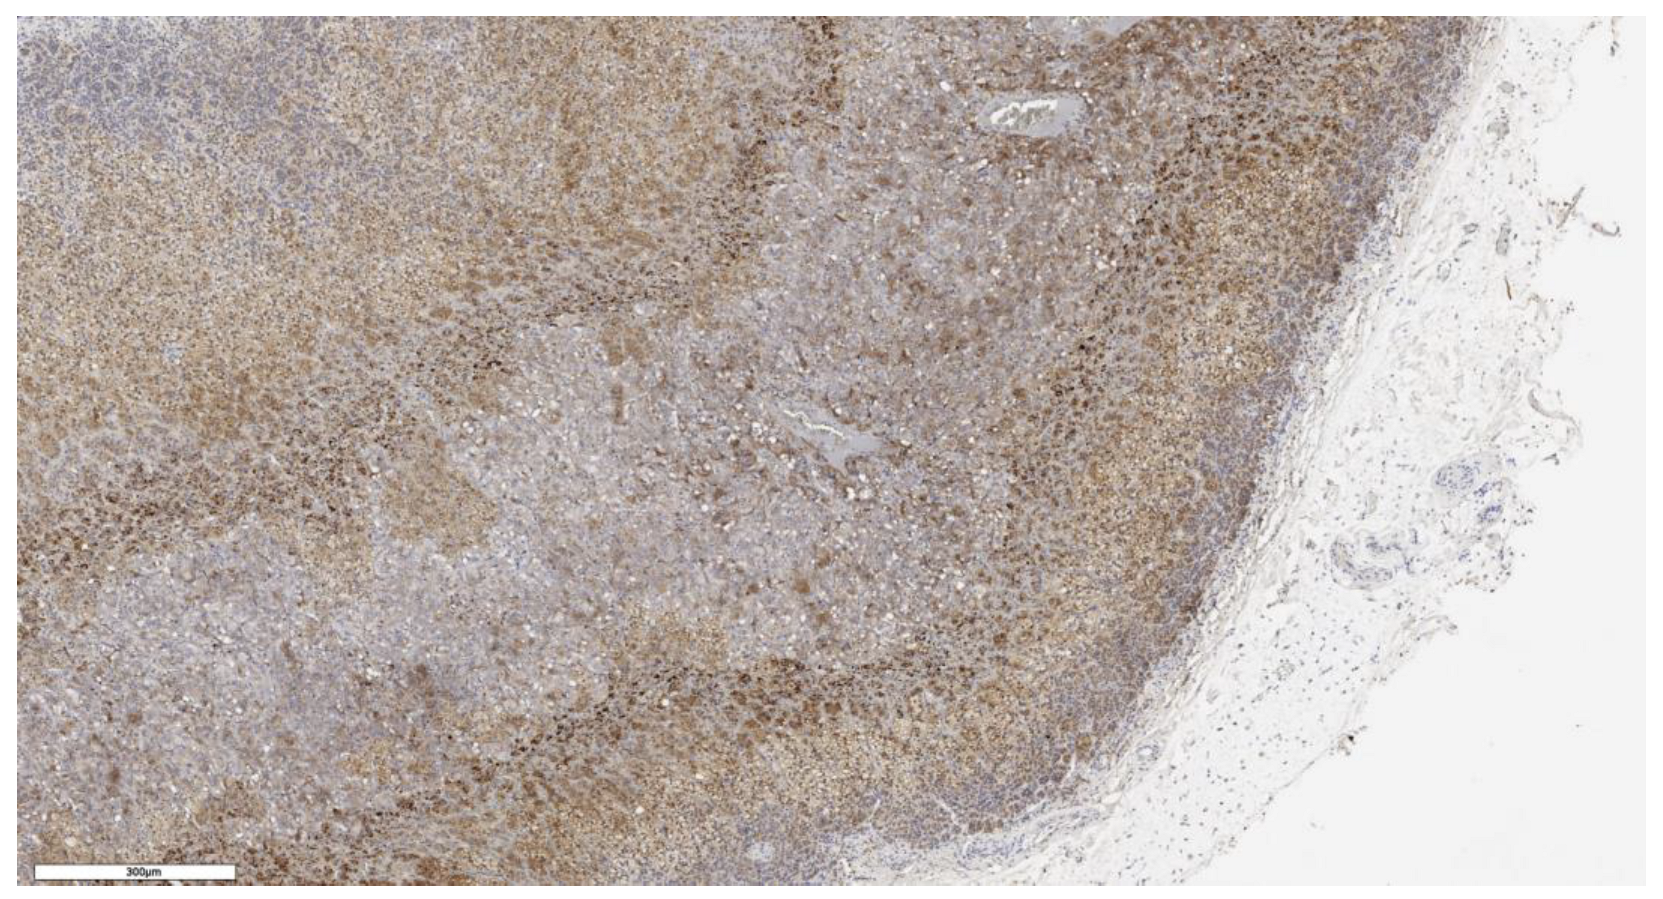

3.1. Analysis of CD90 Marker Expression

3.2. Analysis of LGR5 Marker Expression